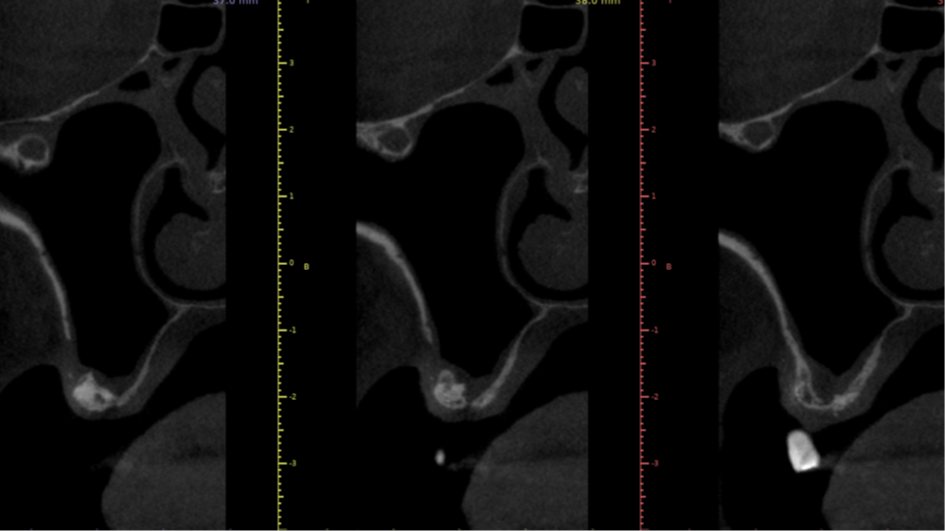

Nas últimas décadas, as reabilitações orais têm sido revolucionadas pela utilização de implantes dentários ósseointegráveis, apresentando uma taxa de sucesso superior a 90%.1 Porém, a maxila posterior edêntula pode dificultar a reabilitação implantossuportada, podendo impor severas limitações anatômicas, causadas pela baixa densidade e possível atrofia do osso alveolar, bem como o processo de pneumatização do seio maxilar.2,3

O processo de pneumatização ocorre devido a atividade osteoclástica da membrana schneideriana em resposta a pressão positiva do ar dentro da cavidade paranasal e a qualidade tipo IV mais macia do tecido ósseo maxilar.4

O presente trabalho tem como objetivo fazer um relato de caso clínico de reintervenção em enxerto ósseo para levantamento de seio maxilar pela técnica da janela lateral com instalação simultânea de implante Maestro Superiore.